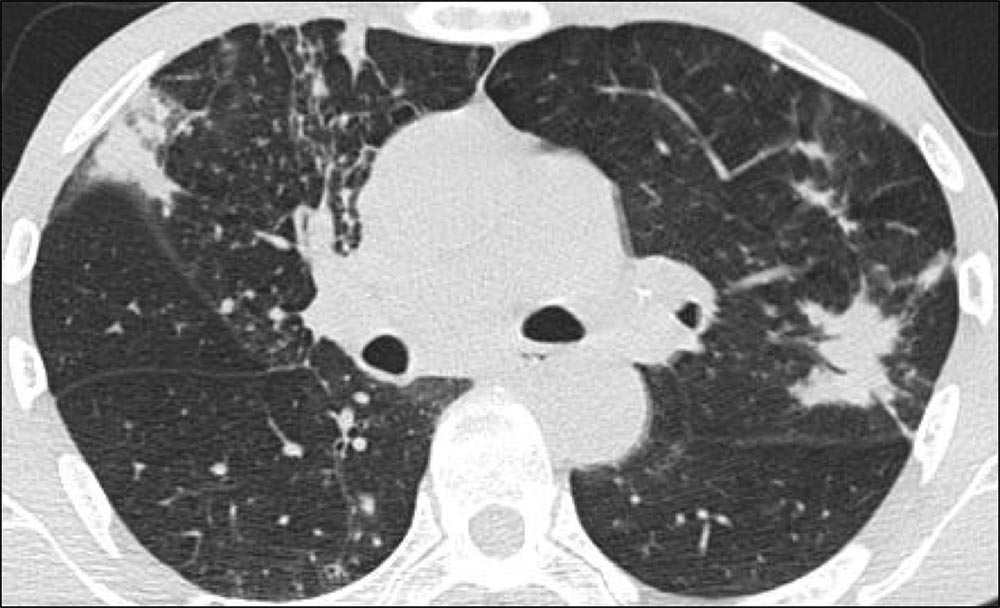

Axial HRCT showing significant honeycombing in a predominantly subpleural pattern at the bases of the lung with peripheral reticulation and traction bronchiectasis. Note the asymmetric pattern of fibrosis, a hallmark feature of usual interstitial pneumonia (UIP).

Image courtesy of and used with permission from Sudhakar Pipavath, MD.